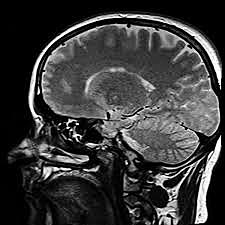

• Resonancia Magnética Nuclear

La resonancia magnética es un fenómeno físico dado por la propiedades de los átomos que tienen un momento magnético y pueden resonar o sincronizarse si se aplica un campo magnético de determinada intensidad y frecuencia.